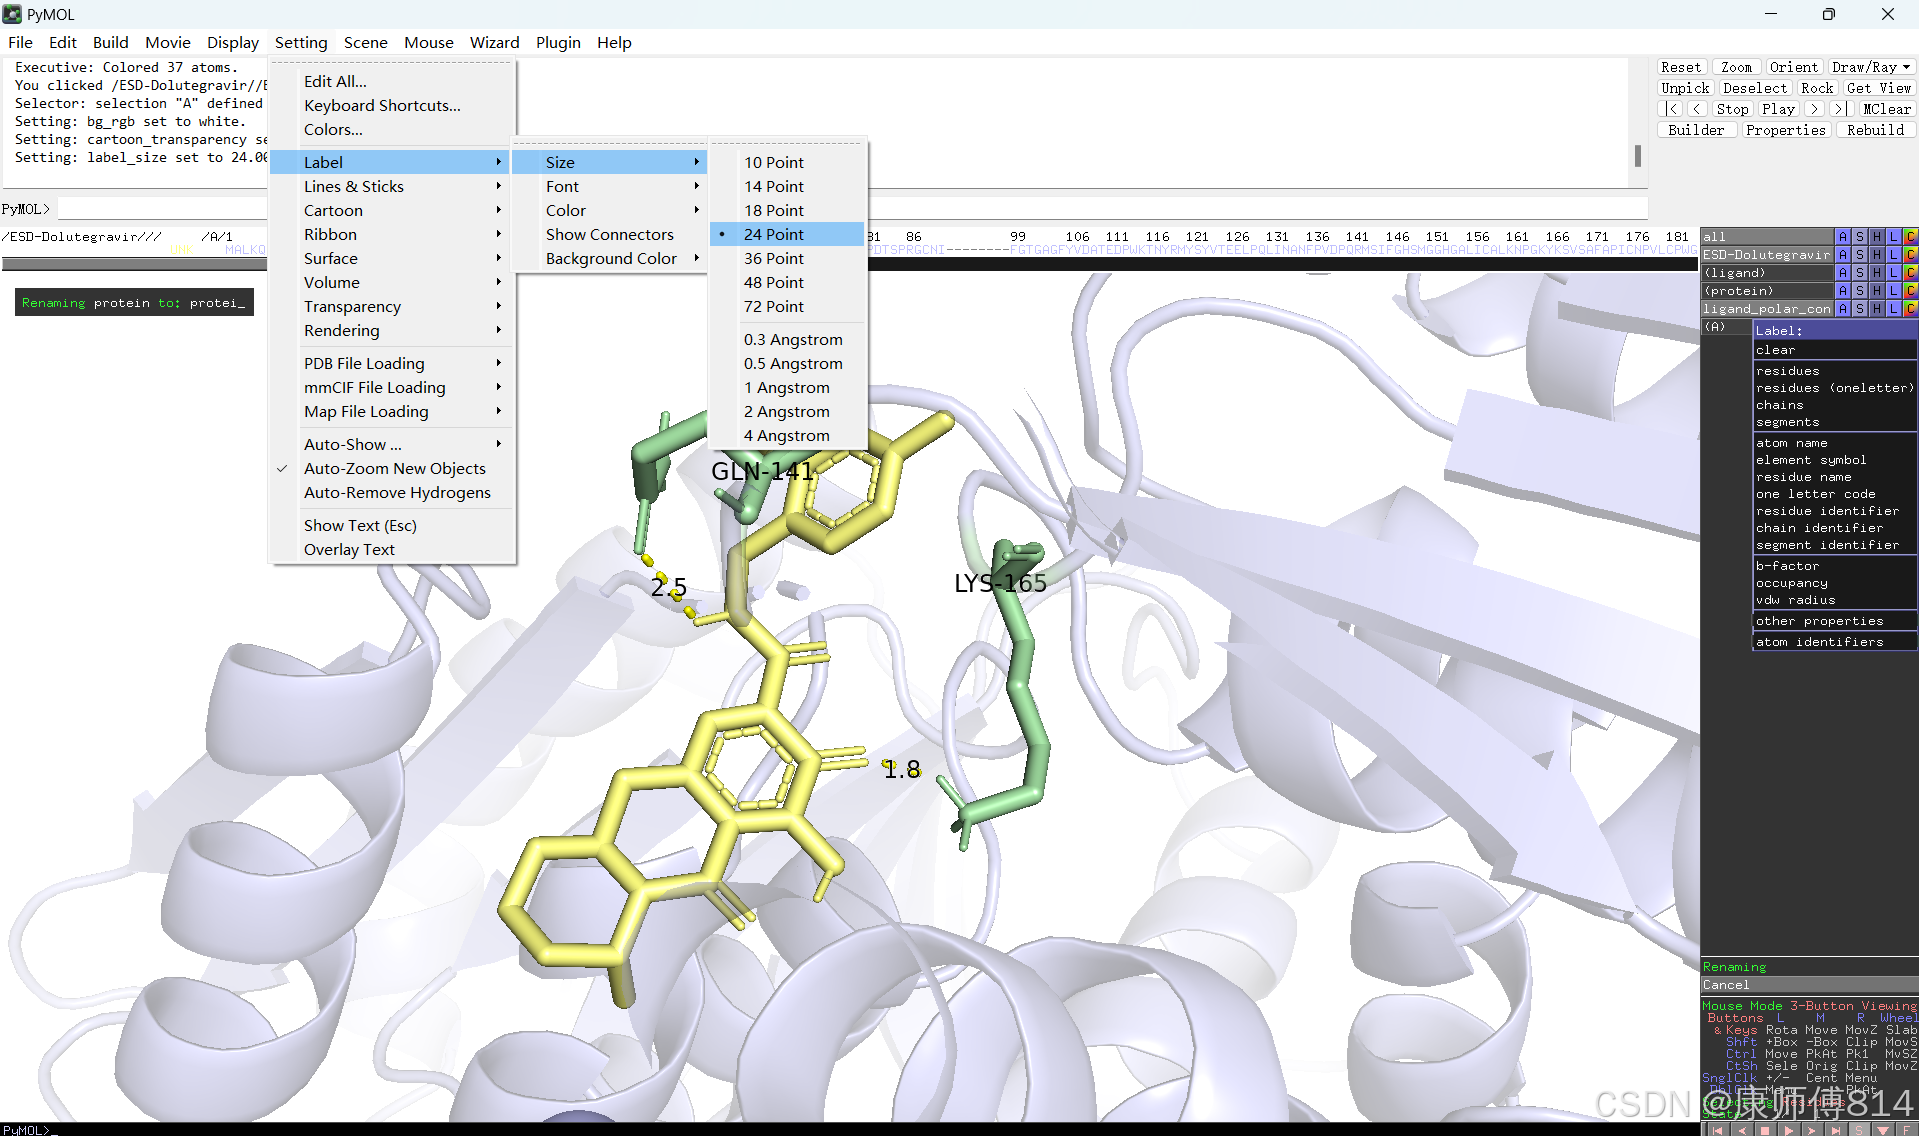

#此时展示分子对接的基本要素已经形成,后续可根据需要修改背景颜色、显示氨基酸残基名字以及氢键键能等等,这里不再赘述

#修改好后就可以导出了,点击右上角Draw,选择合适的格式导出即可